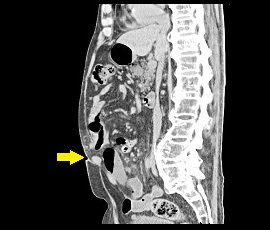

腹痛と嘔吐を主訴に精査加療目的に受診。その前に膵体尾部嚢胞に対して腹腔鏡補助下膵体尾部切除術を施行。 CT検査にて、腹壁にヘルニアを認め腹壁瘢痕ヘルニアと診断。 手術(腹腔鏡下ヘルニア手術)を施行した。

CT画像